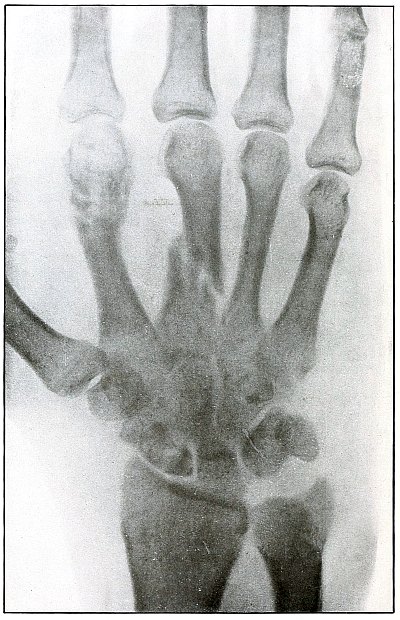

Plate 44.

_

[Pg 99]

Rifle—Plate 44.

UPPER EXTREMITY.

Gunshot Fracture of the Third Phalanx.

The course of the bullet was anteroposterior through the base of the proximal phalanx of the middle finger, with a velocity of long range. It practically punctured the bones and split off a few fragments without displacement.

The wound of entrance would be much the same as the wound of exit, with the latter, but a little larger.

Treatment is conservative. [Pg 100]